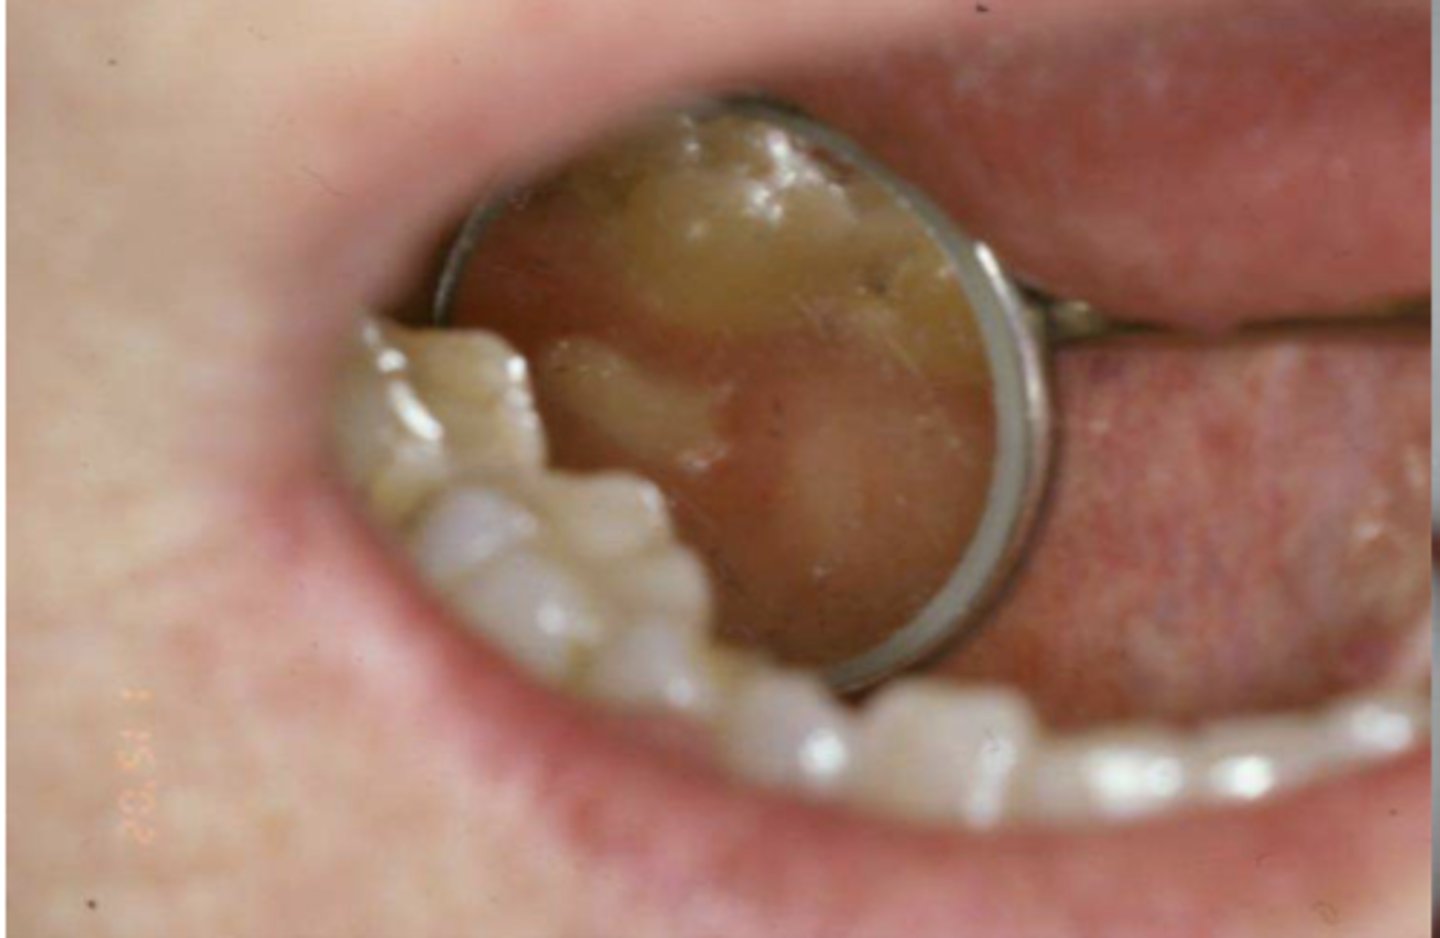

Patient has an RPD. What do you suspect?

inflammatory papillary hyperplasia w/ secondary candidal infection

*can tell pt also has candidiasis b/c of erythema

When the patient removed their complete maxillary denture, you see this. They reported wearing their denture to continuously throughout the day & night. What do you suspect?

what do you suspect?